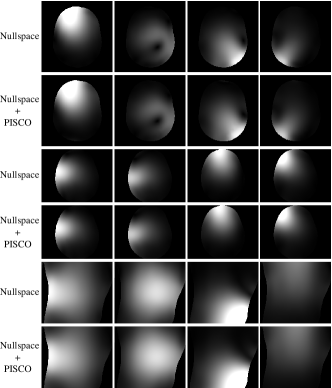

Our empirical results confirm that ESPIRiT and the nullspace-based approach produce identical sensitivity map estimates (up to numerical errors resulting from finite precision arithmetic). To illustrate this, we used in-house MATLAB implementations of both approaches666Note that the naive nullspace algorithm described in Sec. III-D can require an excessive amount of memory that exceeds MATLAB’s limits on the maximum array size. As such, the results we present as the nullspace-based approach in this section actually use one component of the PISCO approach to bypass this issue, namely the efficient calculation of a dimension-reduced matrix instead of the matrix as will be described in Sec. IV-C. to estimate sensitivity maps for all three datasets from Fig. 1 using different amounts of calibration data (ranging from small 2424 calibration regions to larger 256256 regions, always centered at the k-space origin). As a precursor to our description of PISCO in the sequel, we also obtained results from the nullspace-based approach combined with PISCO and ESPIRiT combined with PISCO. Representative qualitative results are illustrated in Fig. 4, which demonstrate negligible visual differences between all four approaches.

Figure 11 compares the results of the Nullspace Baseline against the nullspace-based method with PISCO. In all scenarios, we observe consistently substantial improvements in computation time (up to 100 acceleration in some cases) and substantial improvements in memory usage (even though the Nullspace Baseline already makes use of our computation, which is one of the most memory-saving components of PISCO). Figure 12 shows representative sensitivity maps, which qualitatively demonstrates the strong similarity between the sensitivity maps obtained with both approaches. Detailed numbers for 3232 calibration data were already presented in Tables I-III and support the same conclusions.